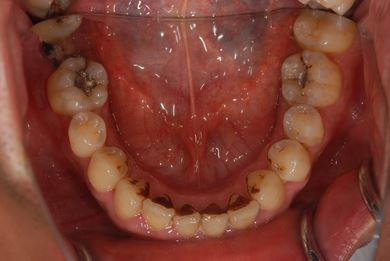

| 性別/年齢 | 男性 / 36歳 | ||||||||||||||||||||||||||||||||

| 主訴 | 歯が折れているので、インプラントにしたい。 | ||||||||||||||||||||||||||||||||

| 治療方針 | 抜歯と同時にインプラント埋入を行い、治療期間を短縮する。 | ||||||||||||||||||||||||||||||||

| 治療内容 | インプラント2本(抜歯即日インプラント治療)、ジルコニアフレームオールセラミッククラウン1本、オールセラミッククラウン2本(セラミック用土台2本)、メタルボンドセラミッククラウン1本 | ||||||||||||||||||||||||||||||||